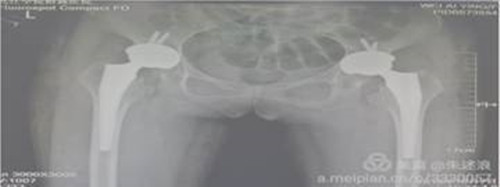

近日,临床医学院/附属医院骨三科成功开展了九江市首例侧卧位DAA微创人工全髋关节置换术,为患者治愈了双侧2度DDH并重度骨关节炎,填补了我市空白。

患者二十余年前开始出现髋关节疼痛,行走后疼痛加重,进行理疗、药物等保守治疗无明显效果,七个月前来临床医学院/附属医院就诊,行盆骨平片检查提示“双侧髋关节半脱位,股骨头缺血性坏死”。临床医学院/附属医院骨三科朱述浪主任带领手术团队为患者实施DAA微创手术,手术非常成功,患者在术后次日便能够负重行走,并保留正常的步态。